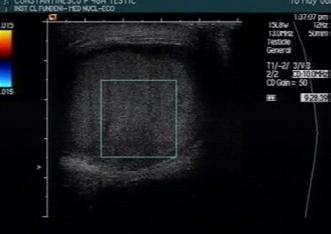

Patternuri de infiltrare a măduvei osoase în MM decelate prin IRM (figura )

Leziunile infiltrative și nodulare întâlnite în MM prezintă hiposemnal T1 datorită absenței grăsimii și cantității crescute de plasmocite din interior; ele prezintă în general un semnal T1 scăzut în comparație cu discurile intervertebrale și musculatura. Pe de altă parte, leziunile prezintă aspect hiperintens pe secvențele T2 FAT SATURATION sau STIR datorită conținutului ridicat de apă și celule, aspect similar altor leziuni osoase maligne[19].

Leziunile MM sunt prezente predominant în scheletul axial și anume vertebre (66%), pelvisul osos (30%) și într-o măsură mai mică la nivelul scheletului extra-axial (coaste, schelet apendicular) [20] În literatură sunt descrise cinci tipuri de infiltrare a măduvei osoase în mielomul multiplu: măduvă cu aspect normal, infiltrare focală a măduvei osoase, infiltrare difuză, infiltrare de tip “sare și piper” și infiltrare combinată focală și difuză [21, 22]; Există o multitudine de studii apărute în literatură care corelează aceste tipuri de infiltrare medulară cu modificările vizualizate la examenele morfo-patologice [23, 24]. În majoritatea cazurilor de MM (28%) se observă un aspect normal al măduvei osoase, cu hipersemnal T1 omogen al acesteia; în cazul infiltrarii, focale se observă diverse leziuni focale T1 hipointense, care pot apărea oriunde la nivelul scheletului; în cazul infiltrării difuze, se observă hiposemnal T1 difuz la nivelul intregii măduve osoase, uneori în caz de infiltrare severă, semnalul fiind chiar mai redus decât cel al discului intervertebral. În doar 3% din cazuri se observă un model de tip „sare și piper” și în 11% din cazuri se poate observa un model mixt de infiltrare nodulară și difuză [22, 25]

Tipuri de afectare medulară în mielomul multiplu: aspect normal imagistic(a), infiltrare focală(b), infiltrare difuză(c) infiltrare de tip ‘sare și piper’, infiltrare mixtă de tip focal și difuz(d). Departamentul de Radiologie al Spitalului Clinic Municipal de Urgență - Timișoara/RO